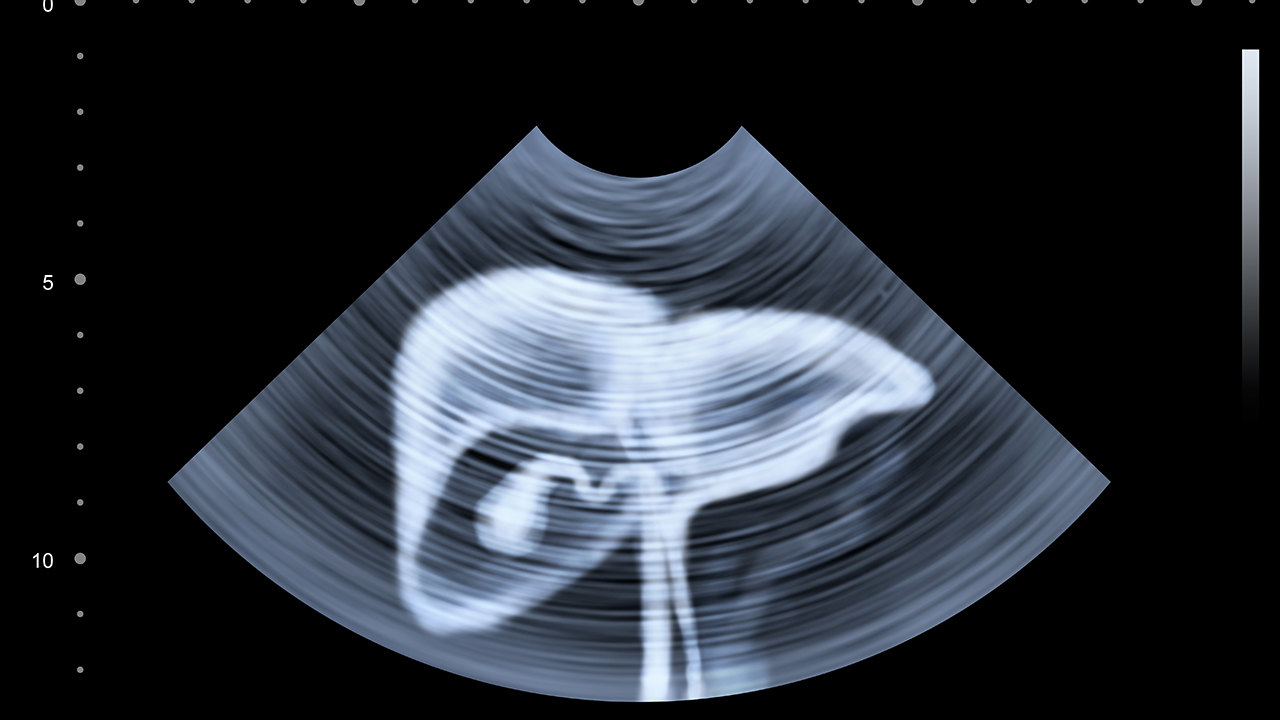

肝癌的预防与健康管理至关重要。对于高危人群,如慢性肝炎患者、肝硬化患者、长期酗酒者等,应定期进行肝功能检查和肝脏超声检查,早期发现病变。保持良好的生活习惯,避免酗酒,注意饮食卫生,防止黄曲霉素污染的食物摄入。对于已确诊的肝癌患者,应积极配合治疗,保持良好的心态,定期复查。同时,接种乙肝疫苗是预防乙肝相关肝癌的有效措施。通过科学的预防和管理,可以降低肝癌的发病风险,提高治果。